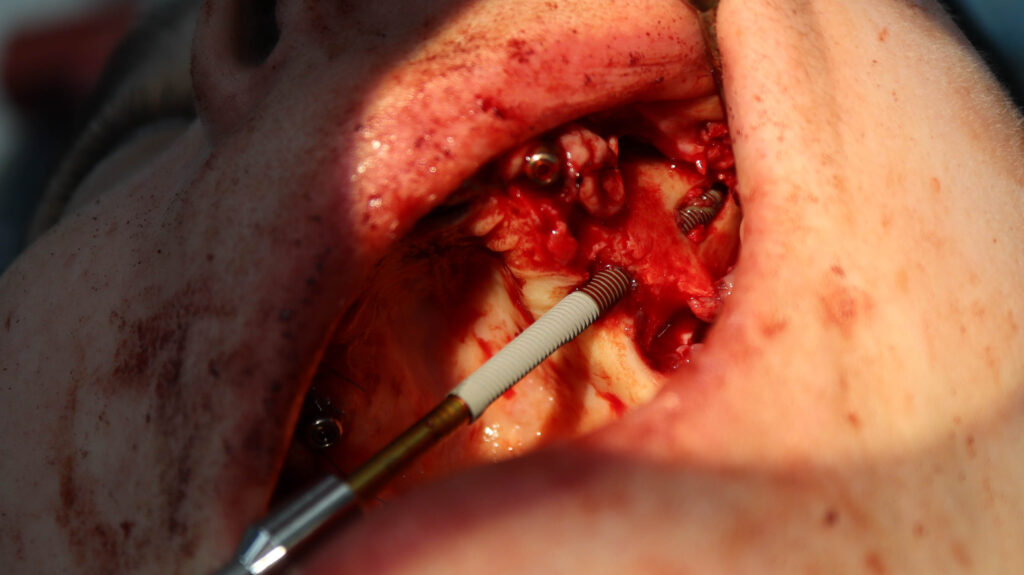

процесс работы

Что было сделано:

На верхней челюсти были удалены зубы, которые находились в неудовлетворительном состоянии, проведена комплексная имплантация по системе All-on-6, установлены 4 имплантата Megagen AnyOne и 2 скуловых имплантата NeoDent.

Фиксации имплантата внутри костной ткани (торк).